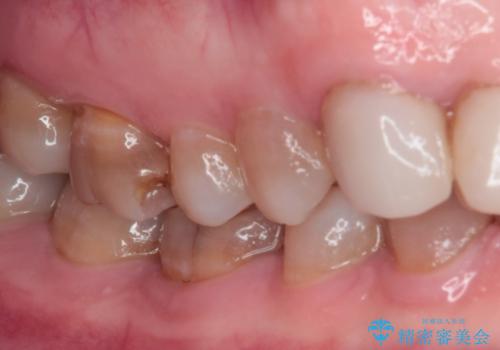

- 前歯の変色や欠損による隙間を気にして来院された患者様です。

上顎前歯は樹脂による変色を覆い隠す処置が行われていましたが、汚れが溜まりやすく厚みも増している状態でした。

上顎前歯は樹脂を外し、下顎前歯の隙間はそれぞれの歯を大きくするように補綴治療を行うことで隙間を埋めることとしました。